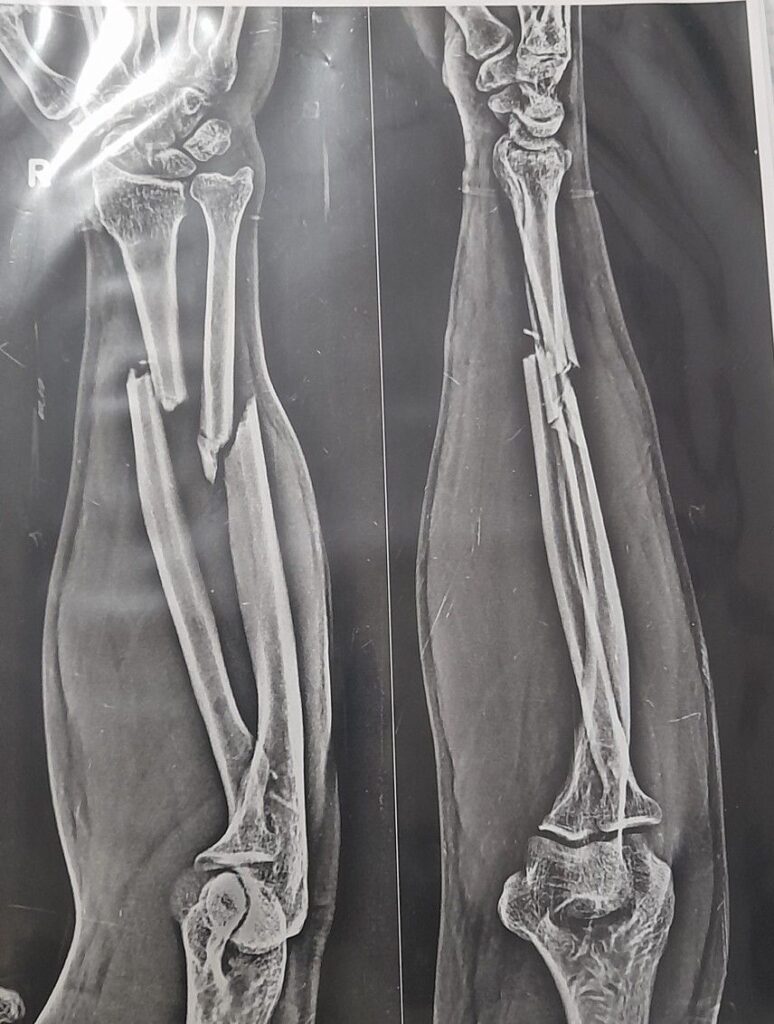

- X-ray (AP and lateral views): Confirms fracture type and alignment

Fracture of the Radius and Ulna refers to a break involving one or both bones of the forearm. These injuries are common in children and adults and can significantly affect hand, wrist, and elbow function. Early diagnosis and suitable rehabilitation are essential for optimal recovery.

- Middle third (shaft) fractures – Involve the diaphysis of the radius and ulna